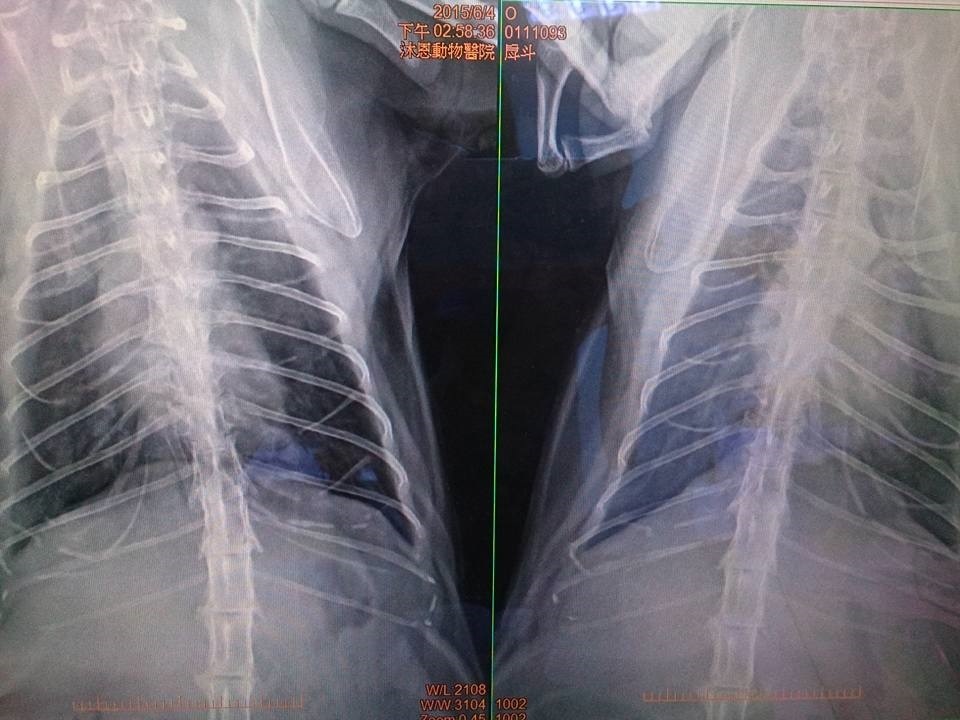

2015/4月起厚道食慾胃口下降,就醫檢查發現肝指數較高,超音波無明顯異狀,X光片肺部較多白影處,可能上呼吸道感染,或者是剛救援時感染肺炎的後遺症,給予口服抗生素,因為厚道的牙齒所剩無幾,又口炎需要噴口樂減緩不舒服,因為肝指數偏高每天需要打皮下點滴75CC補充水分,治療後食慾慢慢恢復,須持續回診追蹤調整用藥。

6/4 厚道回診,肝指數有降些,肺仍有肺部發炎情況已有改善,X光看到心臟旁稍有異樣,建議要掃心超,打水改每天打75ml